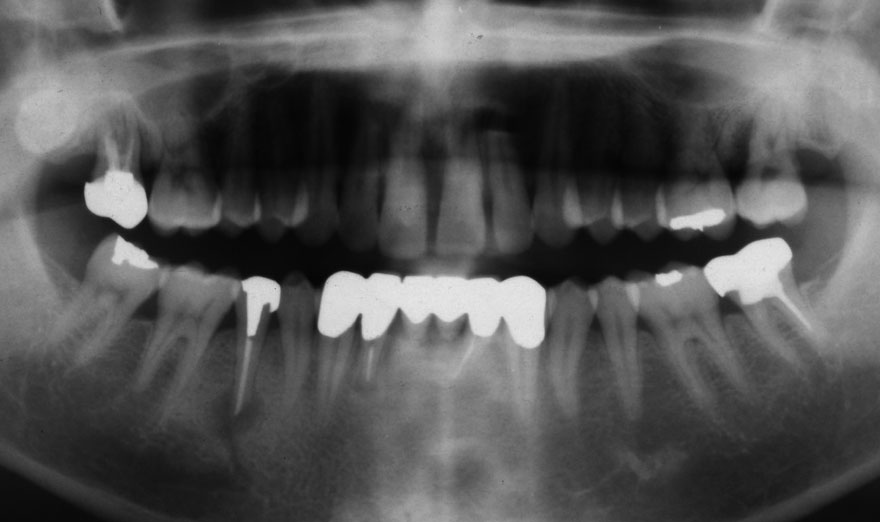

開始年齢 40代

初診時 40歳 女性 平均歯槽骨喪失量:3.14mm

32年後 72歳

平均歯槽骨喪失量:3.22mm

32年間喪失量:-0.08mm

年間喪失速度:-0.002mm

(ケア頻度:1.86ヵ月ごと)